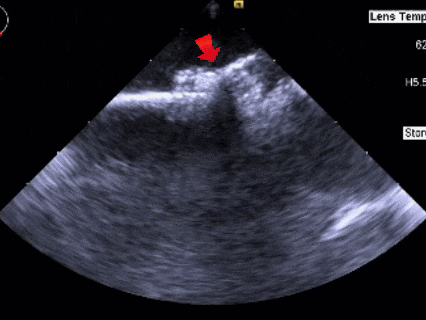

送入鞘管

鞘管配合加硬导丝顺利通过缺损,可见双轨征